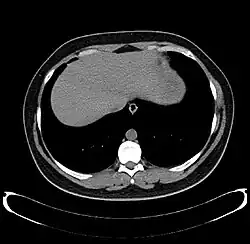

-

Axial CT image showing anomalous hepatic veins coursing on the liver's subcapsular anterior surface[74] -

Maximum intensity projection (MIP) CT image as viewed anteriorly showing the anomalous hepatic veins coursing on the anterior surface of the liver -

Lateral MIP view in the same patient as previous image -

A CT scan in which the liver and portal vein are shown